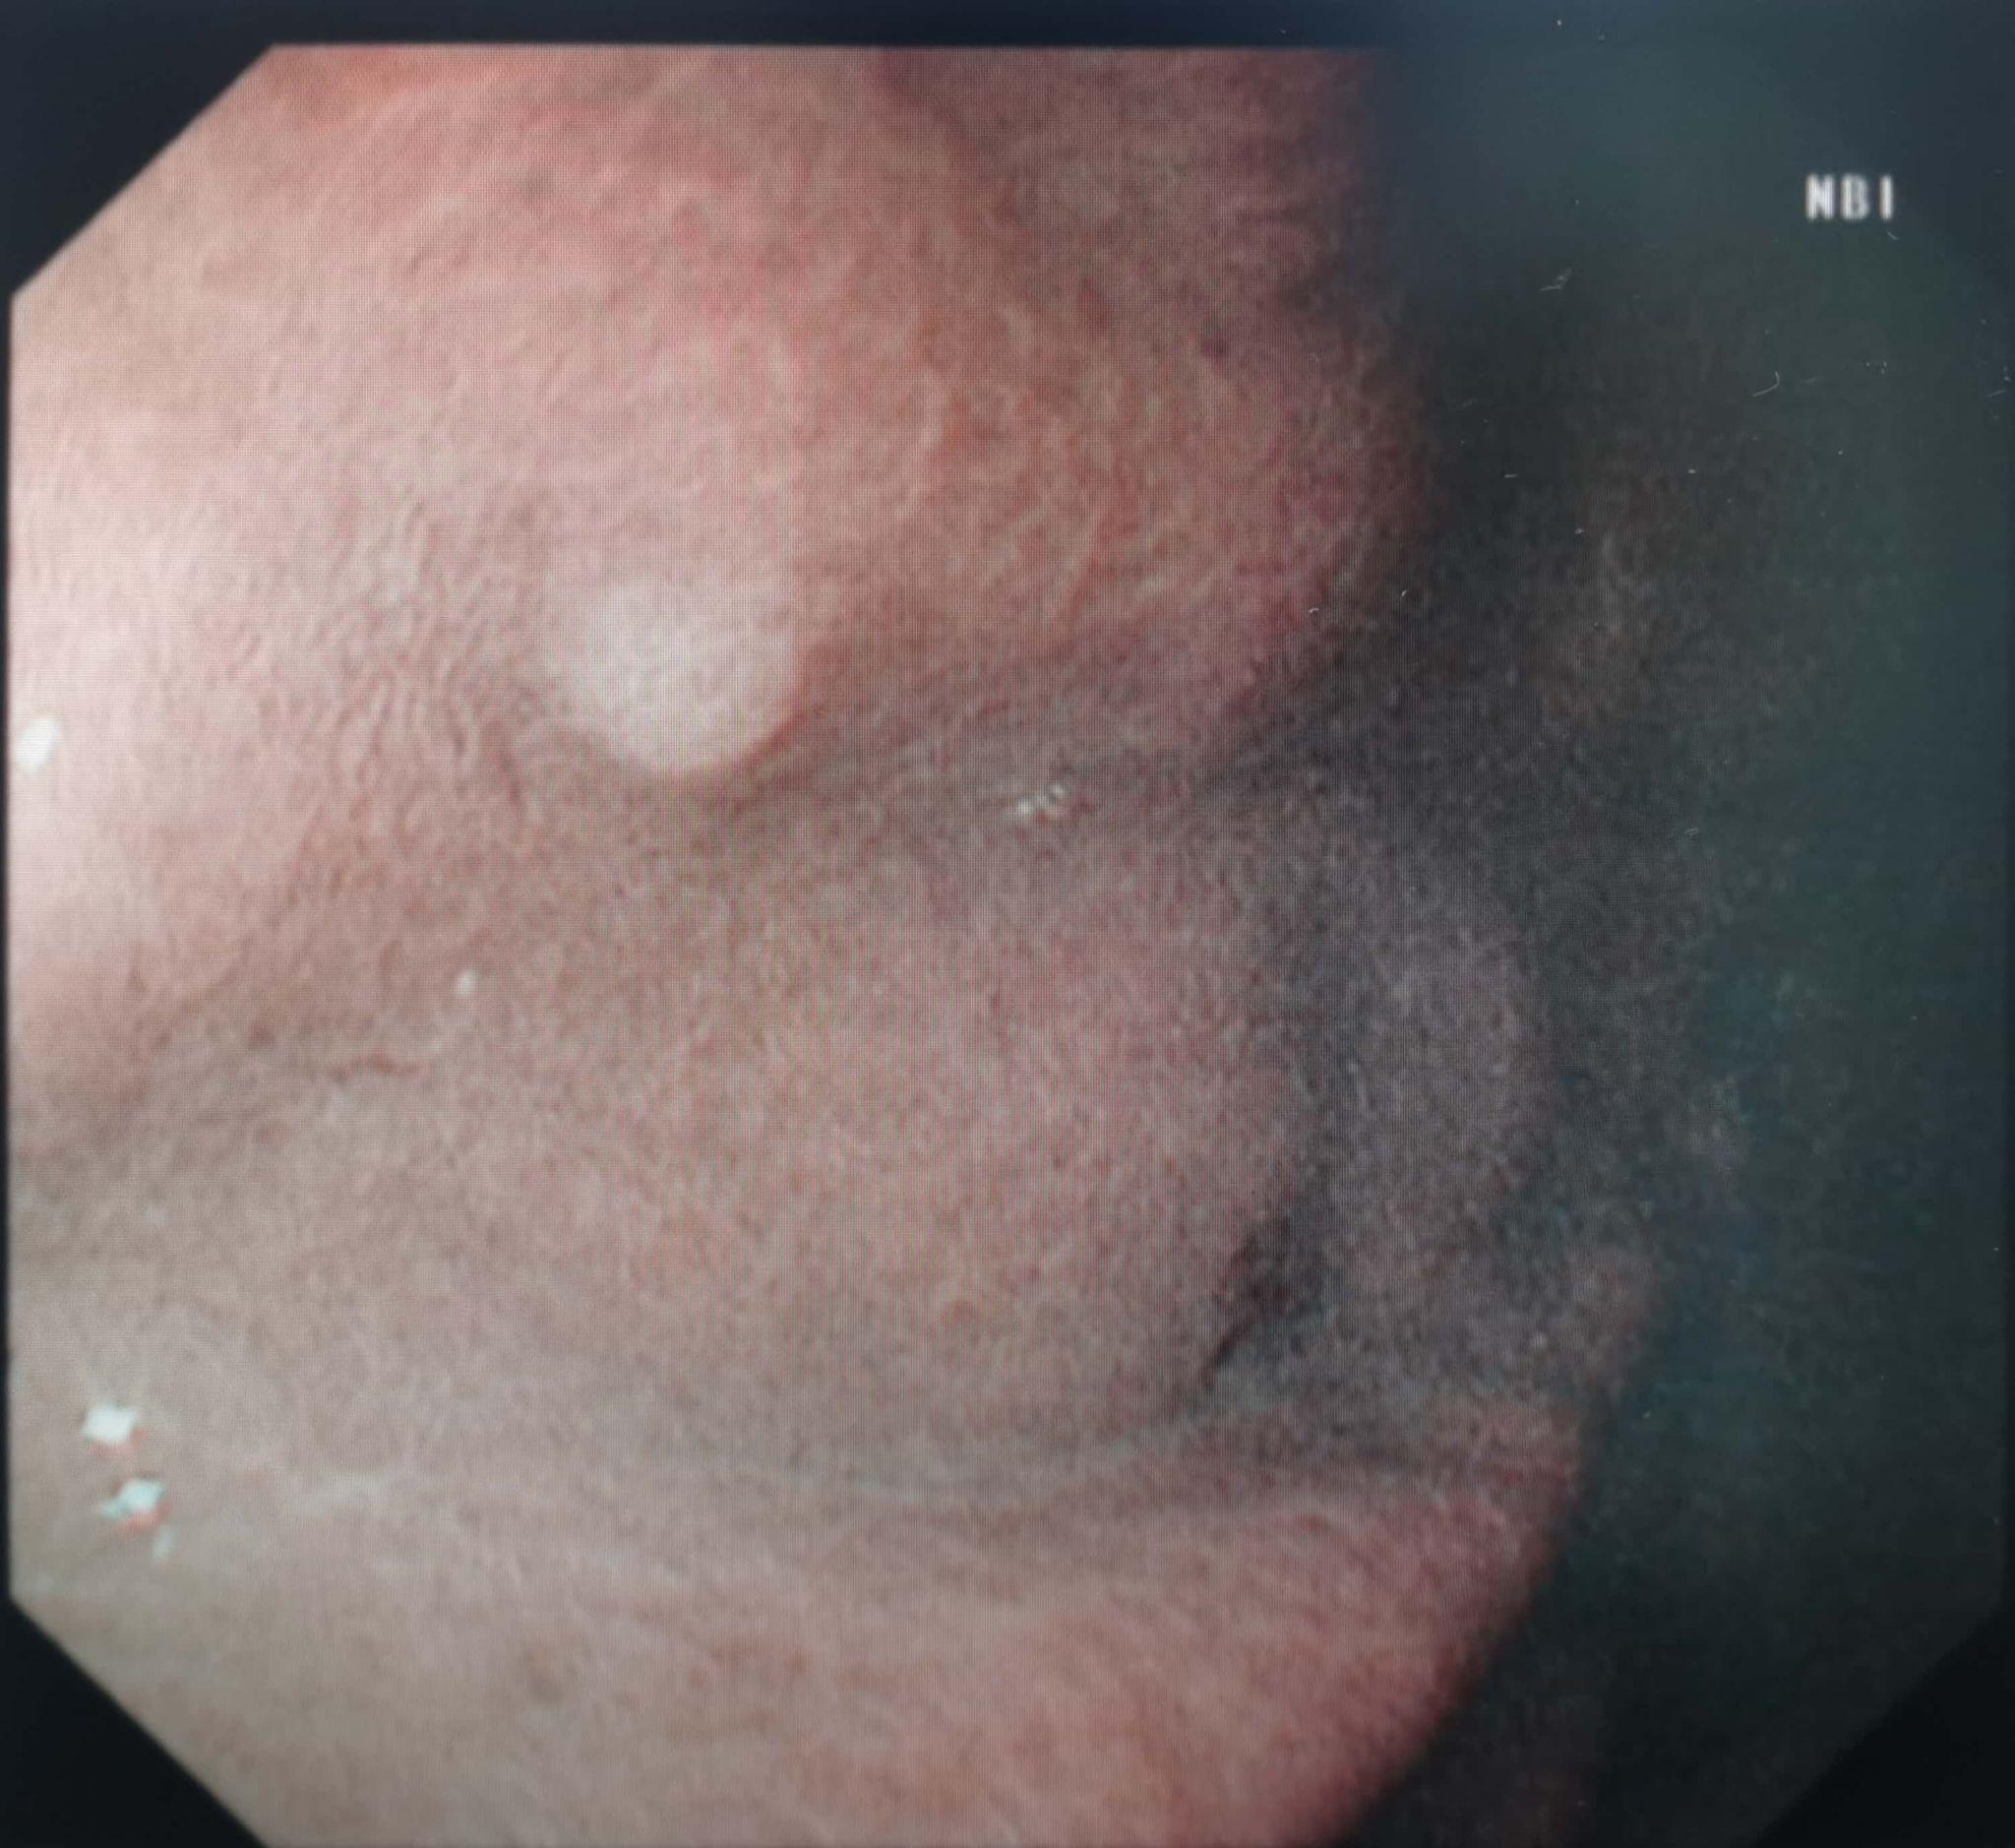

胃息肉的严重性不能一概而论,需根据类型和特征综合判断胃底腺息肉炎性息肉和增生性息肉通常不严重这类息肉多为良性病变,一般无恶变倾向其形成多与慢性炎症刺激或胃酸分泌异常相关,临床表现为黏膜局部隆起,直径多小于1厘米通过内镜下切除如高频电凝圈套器电切可完全治愈,术后复发率低。

症状表现存在个体差异部分患者可能无明显不适,但另一些患者可能出现消化不良胃痛胃胀反酸或黑便等症状症状的严重程度与息肉位置大小及是否引发并发症如出血梗阻相关诊断需依赖专业检查胃镜是发现和评估胃息肉的主要手段,可直接观察息肉数量大小形态及表面特征组织病理学检查是。